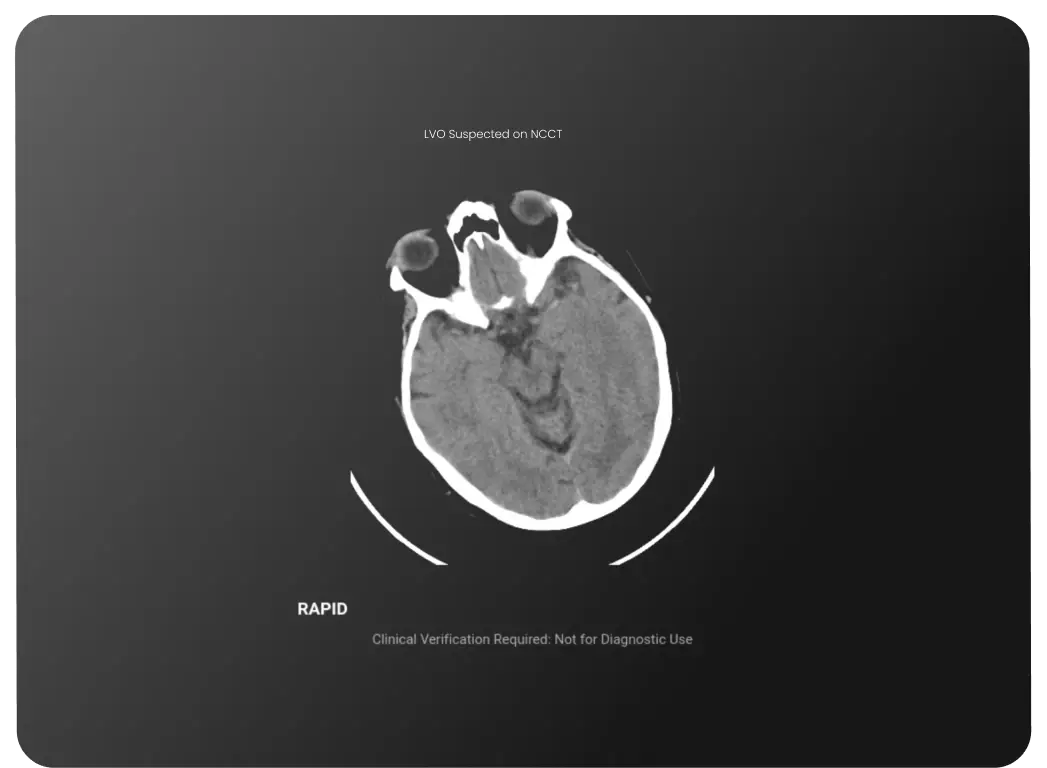

AI-driven Worklist Prioritization

Keep urgent cases at the forefront.